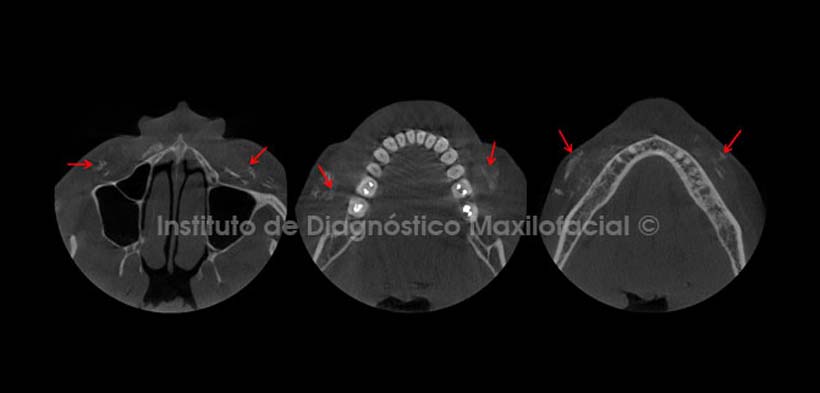

Por otro lado, las vistas axiales nos muestran la presencia de estas calcificaciones en diferentes niveles del complejo maxilofacial, observando además su cercanía a la superficie del tejido óseo en la vista más superior y a la superficie del tejido blando en la vista más inferior (Fig. 2).